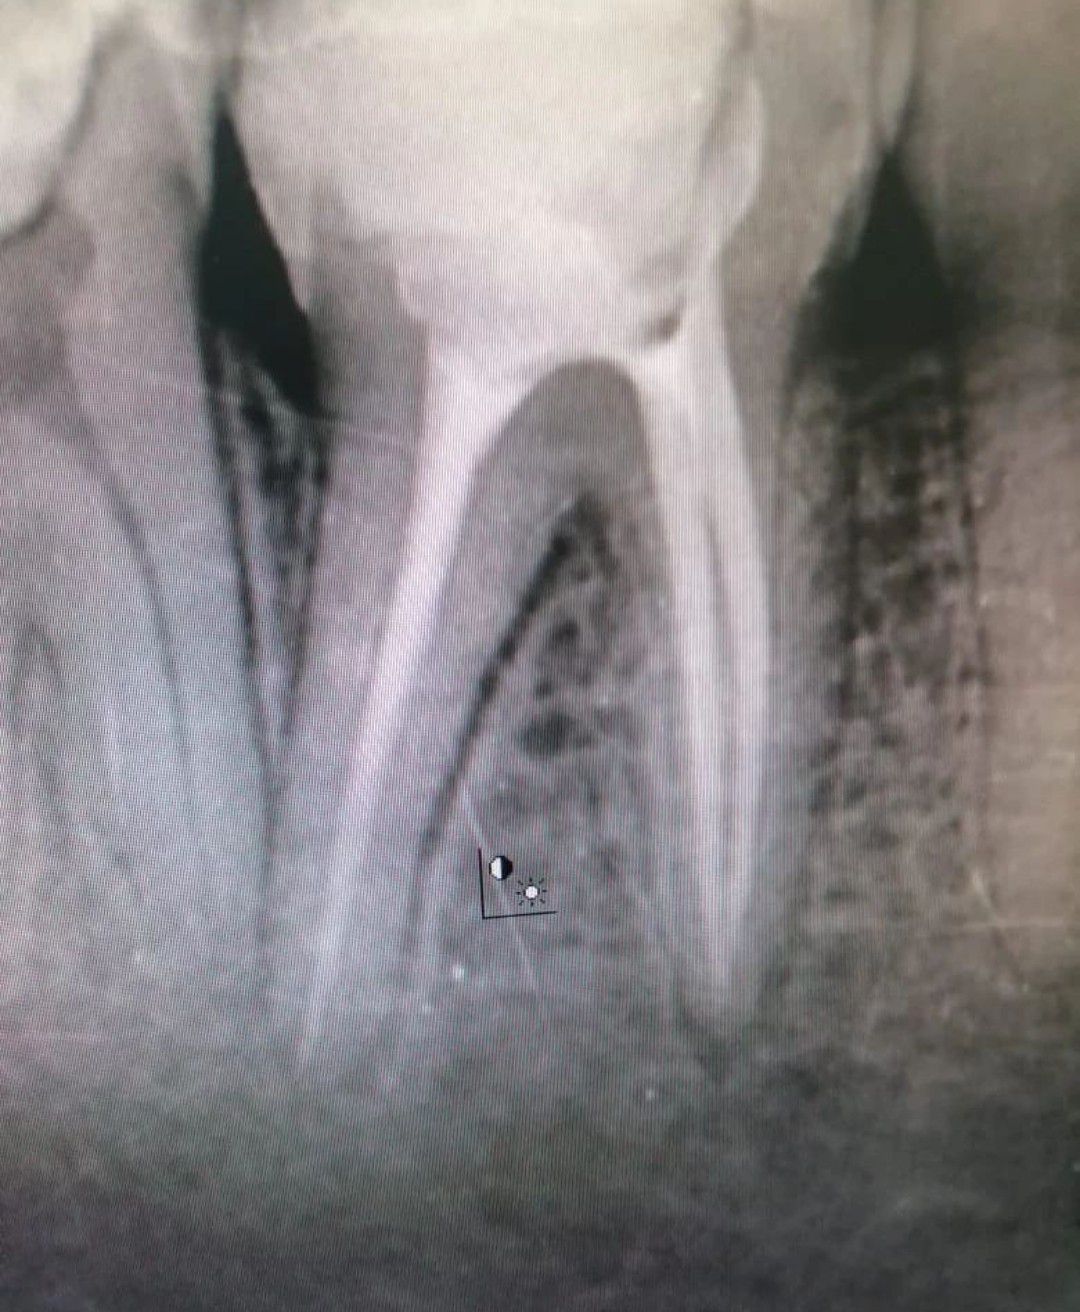

Here are the steps that will be completed during your root canal procedure: Anesthesia. First, local anesthesia is given to numb the infected tooth and the surrounding gums. ... Dental dam placement. ... Access hole. ... Pulp removal. ... Shaping the canals. ... Filling the canals. ... Sealing the tooth. ... Placing the final restoration.